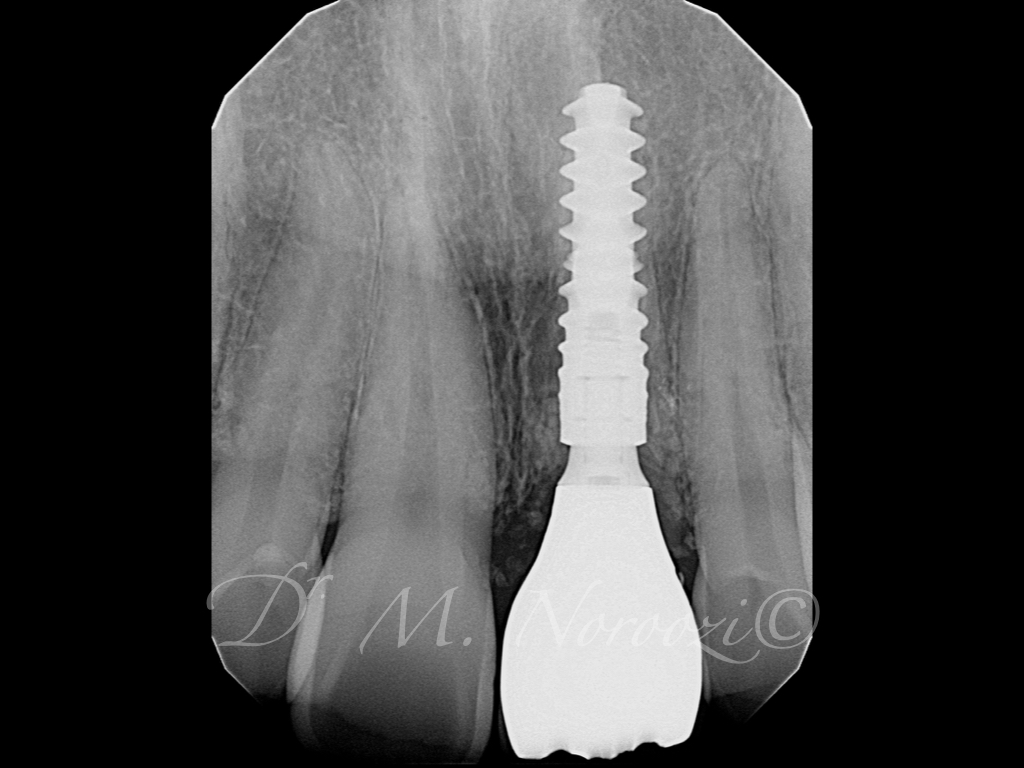

When you lose a tooth, you lose both the root and the crown. To replace the tooth, the surgeon first replaces the root with a  dental implant. Time is allowed for bone to heal and grow around the dental implant. The bone bonds with the titanium, creating a strong foundation for artificial teeth.  A support post (abutment) is then placed on the implant and a new replacement tooth (crown) is placed on top of the abutment. In many cases, a temporary replacement tooth can be attached to the implant immediately after it is placed. If all of your teeth are missing, a variety of treatment options are available to support the replacement teeth.

• Your specialist will carefully examine your mouth and take x-rays of your head, jaw, and teeth to find out if dental implants are right for you.

• During the first stage of surgery, your dentist or specialist will put a dental implant into your jawbone beneath the gum tissue. The gum tissue is then stitched back into place. As the tissue heals, the implant will bond with the bone and attach to the gum. It can take several months to heal.

• During the second stage of surgery and once the tissue is healed, your dentist or specialist will attach an abutment to the implant. An abutment is a post that connects the replacement tooth to the implant. In some cases, the first and second stage of implant surgery may be done in one single stage.

• An artificial replacement tooth is made and your dentist or specialist attaches it to the abutment. It may take several appointments to properly fit the replacement tooth to the abutment.

General Disclaimer: The results in the photographs are examples only and do not imply any certainty of the result of a procedure, and all outcomes are subject to the circumstances of the individual patient.